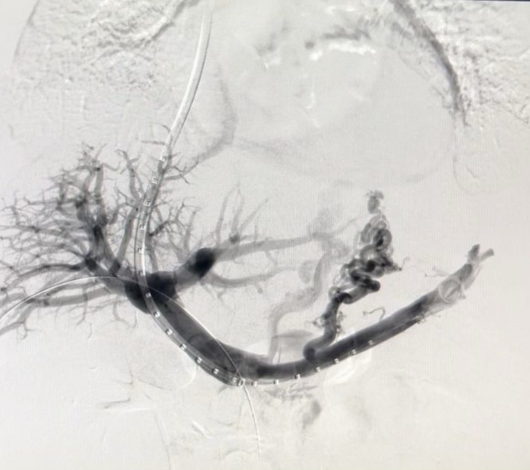

Derivación intrahepática transyugular portosistémica (TIPS)

Es un procedimiento que consiste en crear un canal artificial dentro del hígado conectando la vena porta con una vena hepática.